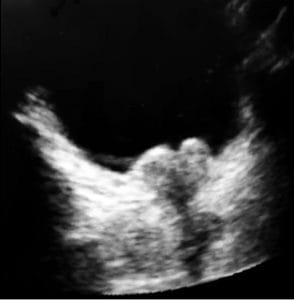

A 68-year-old woman with decompensated alcoholic cirrhosis presented to the hospital with altered mental status and acute kidney injury in the setting of medication noncompliance. She was determined to have hepatic encephalopathy and poor renal perfusion secondary to abdominal compartment syndrome. Our inpatient procedure service was consulted to perform a large-volume paracentesis. Following standard protocol, ultrasound-assisted paracentesis was performed in the left lower quadrant after identifying free-flowing ascites approximately 10 cm in depth (Figure 2a). After initial drainage of 1.1 L of clear, yellow fluid into evacuated containers, flow through the paracentesis catheter abruptly terminated. Given ongoing physical exam findings of a tense, distended abdomen, and pre-procedural insonation of significant peritoneal fluid, obstruction of flow through the catheter was suspected. POCUS performed with sterile technique demonstrated attachment of bowel with retraction of the catheter (Figure 2b; Supplemental Video S1).

Figure 2. 68-year-old woman with decompensated alcoholic cirrhosis. A) Pre-procedural POCUS exam demonstrating large volume ascites in the left lower quadrant of the patient described in Case 2. B) Intraprocedural POCUS exam demonstrating attachment of omentum/bowel to the paracentesis catheter. [Arrow = catheter]